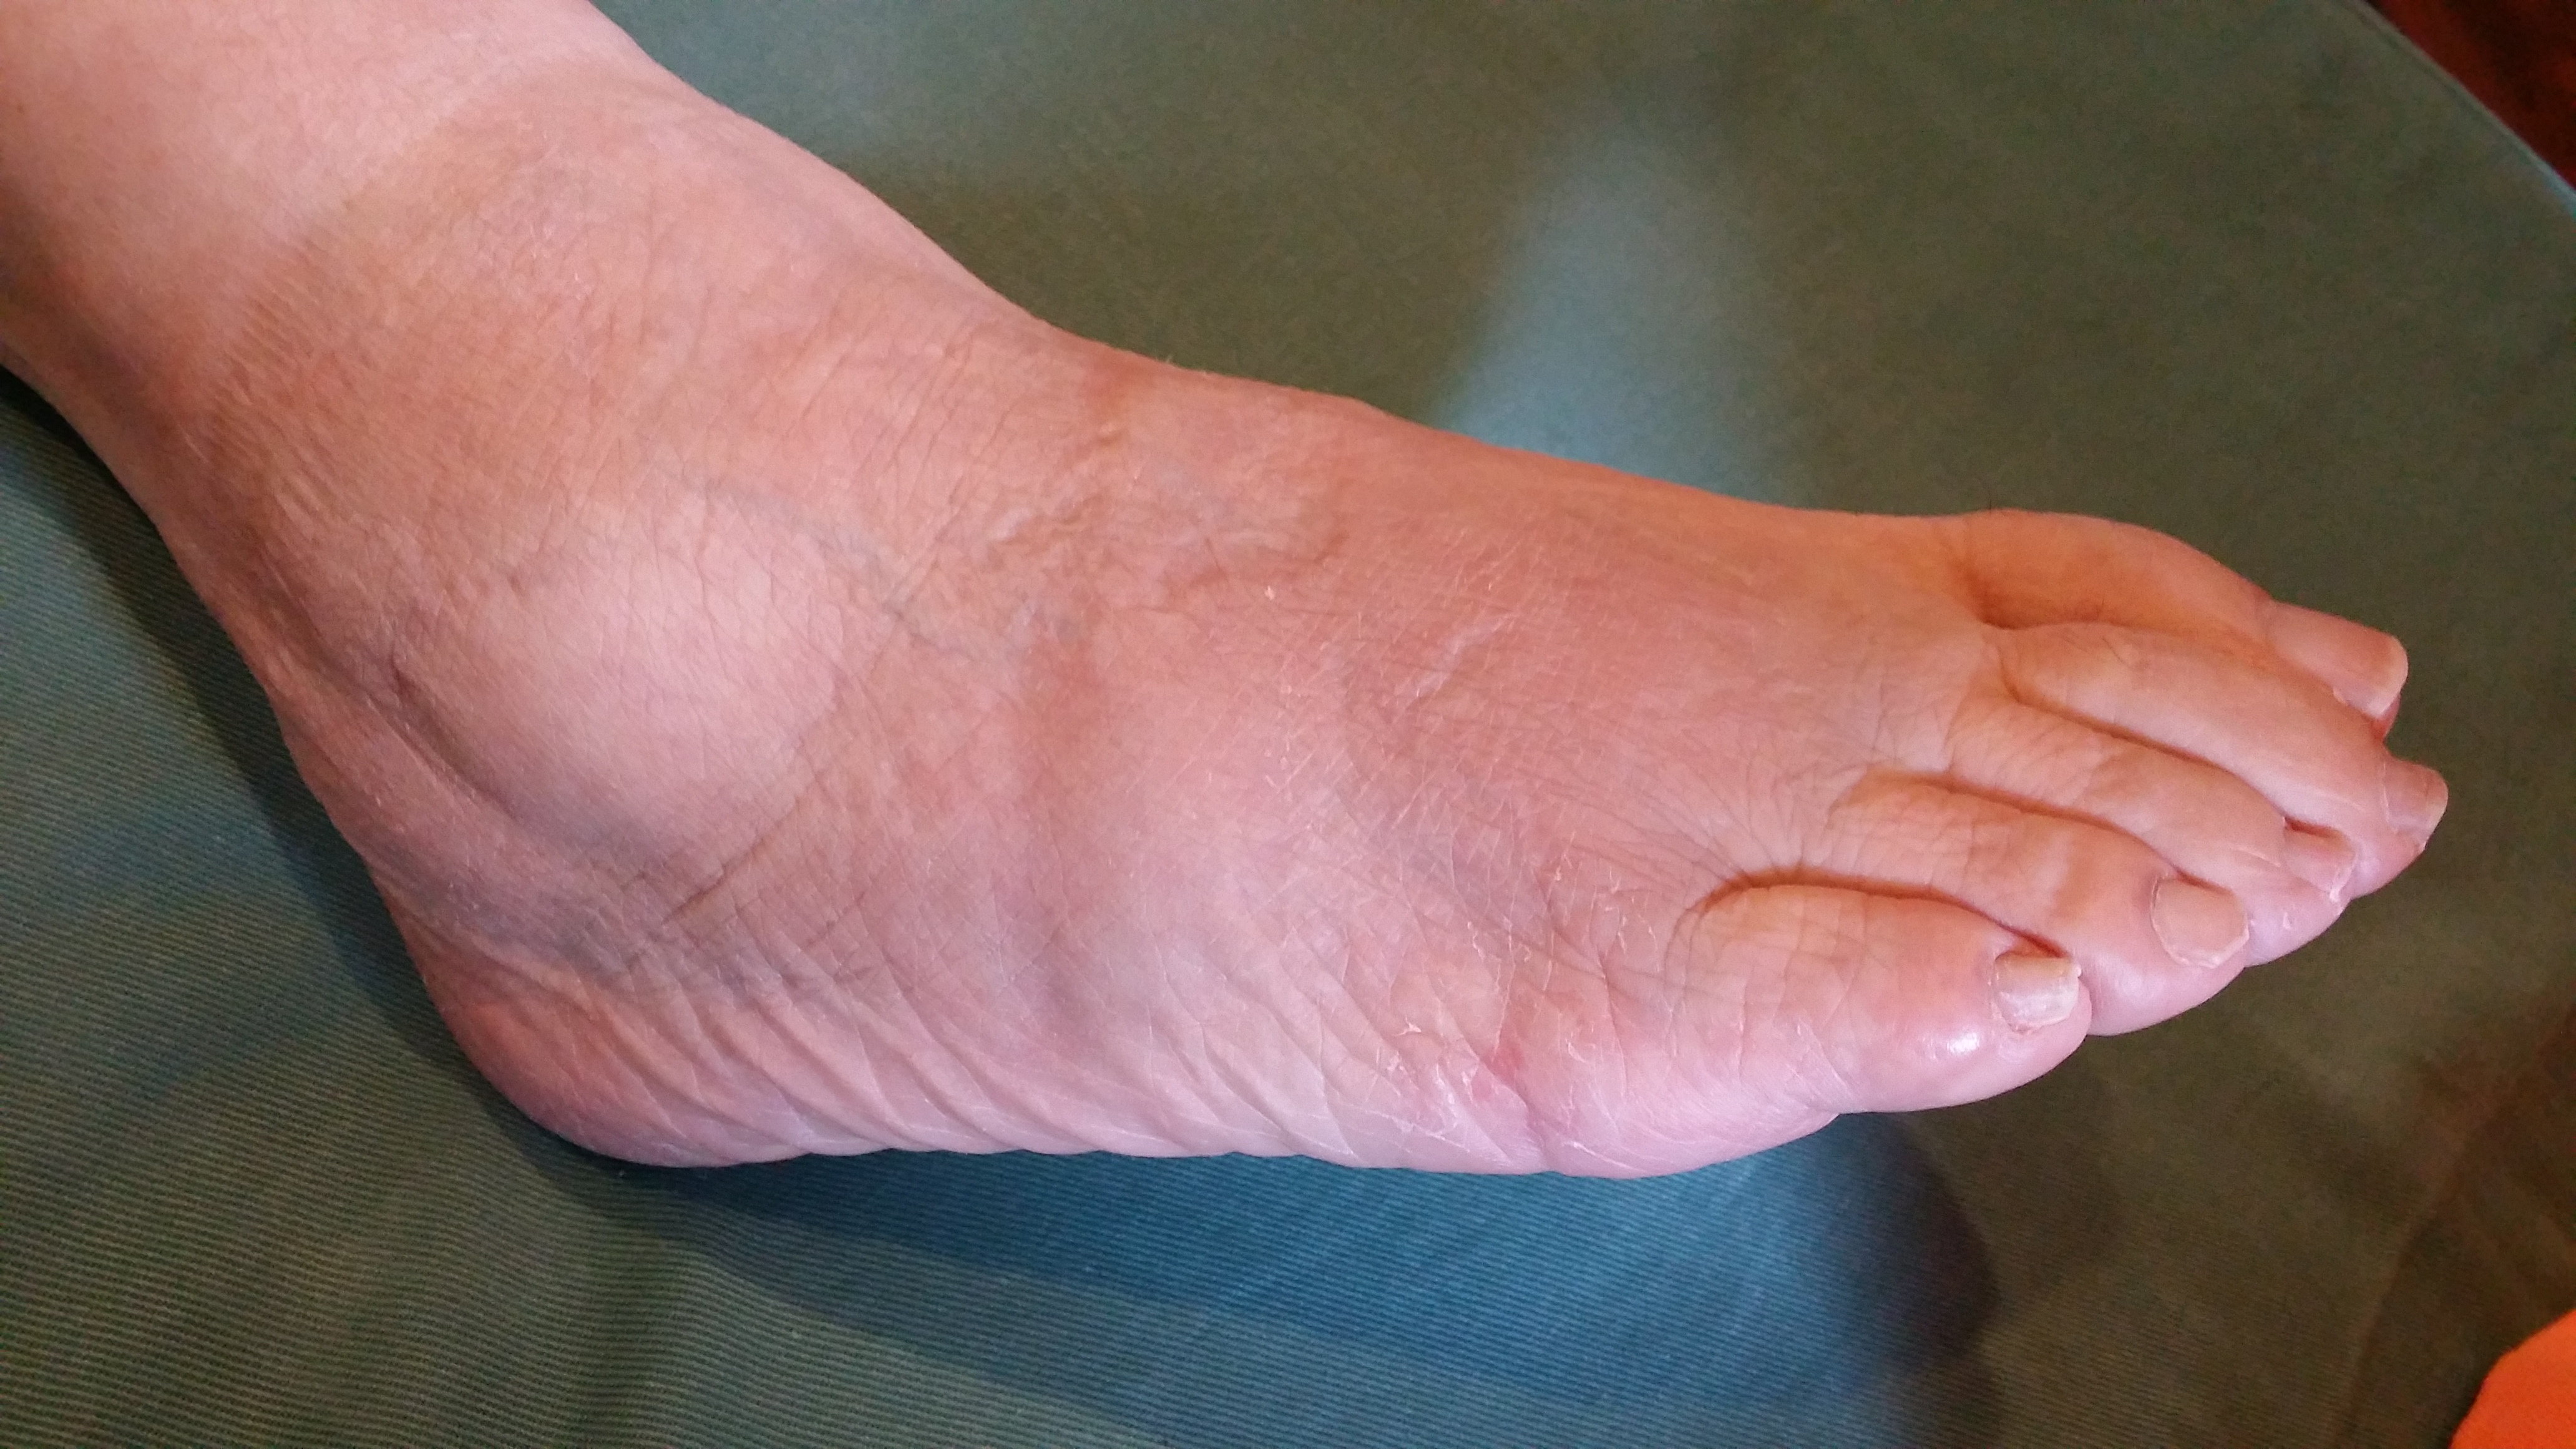

皮下出血、腫脹(はれ)が少なく荷重時の痛みが軽度訴えるのみである。

捻挫と判断しようと思ったが、レントゲン撮影を依頼すると